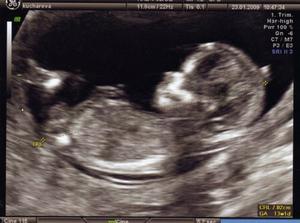

V květnu 2008 jsem dobrala posledni pilulku antikoncepce a začalo krásné snažilkování.Netrvalo to ani moc dlouho,ale jako správná zdravotní sestřička jsem viděla už všechny ty hororové situace a podobně,takze jsem při každé mrše byla čím dál tím více nervozní.Známá mi doporučila pít čajik a kontryhelu a řebříčku na podroru těhu a ejhle povedlo se.2. prosince mi p.Dr.potvrdila těhu...tolik radosti.Mimis roste jako z vody a vypada to ,že to bude lvíček po taťkovi i mamce,takže taková malá lví rodinka 🙂.Asi v 11tt nas cekalo male prekvapeni a to ze mame dva gestakcni vacky ,ale ten jeden malinky se nam po tydny vstrebal takze syndrom mizejiciho dvojcete ☹ ,ale aspon ze nam ten jeden bojovnicek zustal a muzeme se tesit dal.Všechna vyšetření mamé o.k. jen na velkém USG jsme byli otočení zadečkem,takže jsme vlastně nic neviděli.

Dneska 7.4. probehla dalsi kontrola no a opet jsme se nic nedozvedeli jelikoz nas mimisek si porad hovi zadickama a prdelkou k USG ach jooooooo.mamca je trosku zklamana jelikoz nevime ani jak je velike atd ale pani doktorka tvrdi ze je vse O.K...........tak snad to tak je 🙂 v patek 17.4 jedema na kontrolni USG do Olomouce,tak snad se tam dozvime vic...............

Tak jsem byli v poradne jsem 32tt a konecne jsem se neco poradneho dozvedeli a to ze mame 1,5 kila a merime 38cm pry nejsme zadni macci ale ze je to v norme,takze asi budeme mit drobnejsi miminko,pan dr.videl i pohlavi ,ale mamca se premohla a nezeptala se.....ale musela se sebou pekne bojovat aby to vydrzela🙂....